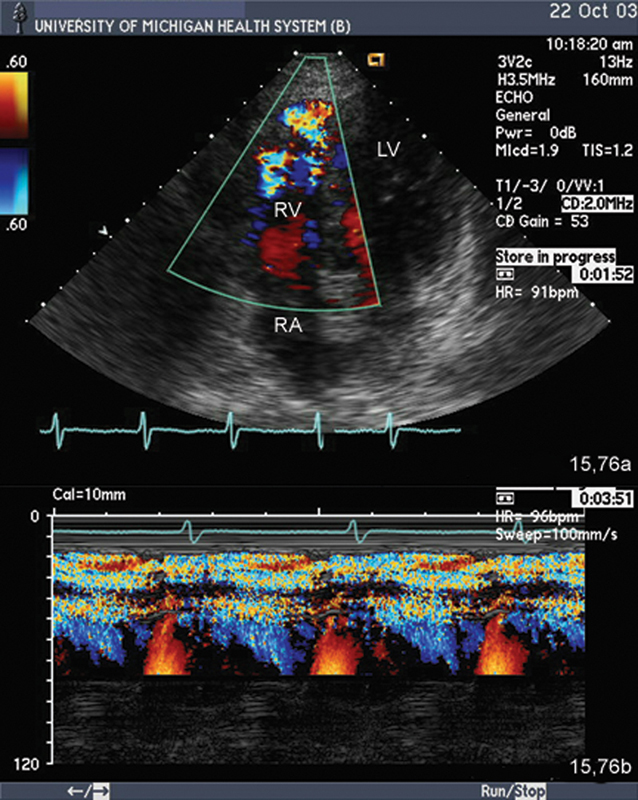

فحوصات تشخيصية لبعض امراض القلب والشرايين التاجية